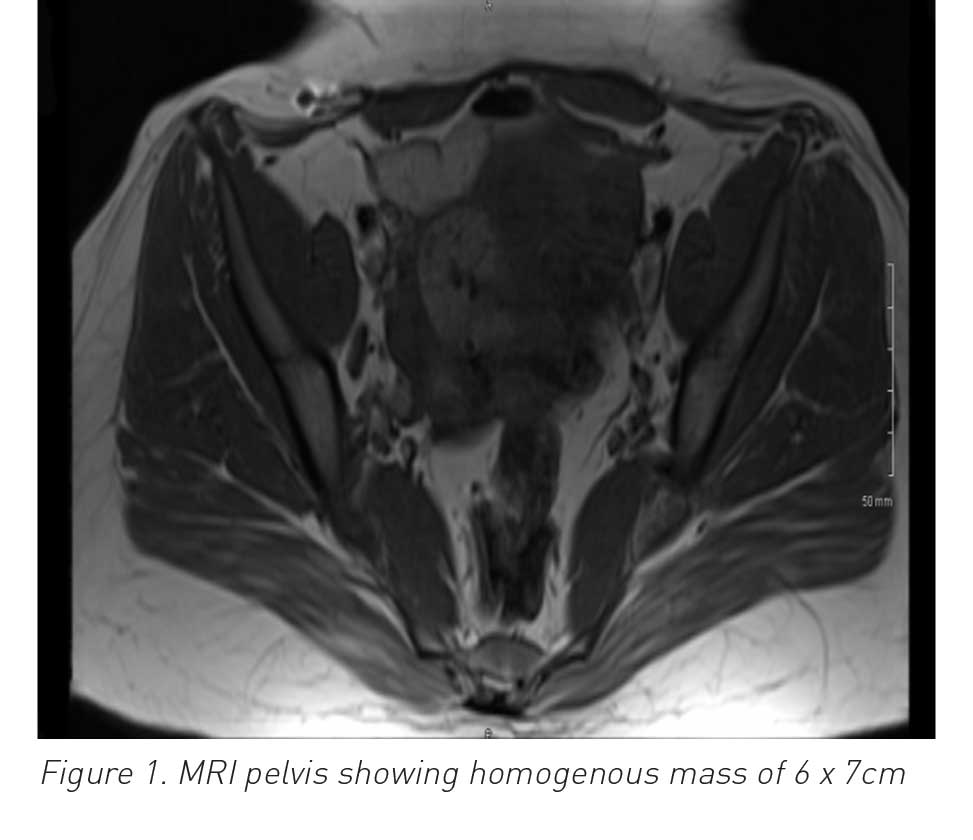

Uterine arteriovenous malformation (AVM) is defined as abnormal and nonfunctional connections between the uterine arteries and veins. Although rare, it is a potentially life-threatening condition. Fewer than 100 cases are reported in existing literature and include patients who presented with per vaginam (PV) bleeding, often mild to moderate, but sometimes life-threatening. It is likely to occur during a woman’s reproductive years and treatment depends on signs and symptoms, as well as future fertility requirements. If symptoms are not improved with conservative treatment, uterine artery embolisation is required to avoid the need for a hysterectomy.

This report looks at a case of acquired uterine AVM, confirmed by angiography, which was successfully treated with bilateral uterine artery embolisation.

There are two types of AVM in the uterus: one is congenital and the other is acquired through previous uterine trauma (eg. curettage or previous pelvic operations), infection or trophoblastic disease. Congenital AVM is extremely rare, whereas acquired AVM is increasing in incidence. This rare condition occurs most frequently in women of reproductive age. Such women present most commonly with PV bleeding but some present with life-threatening bleeding. Management of AVM is mostly conservative but may necessitate embolisation.